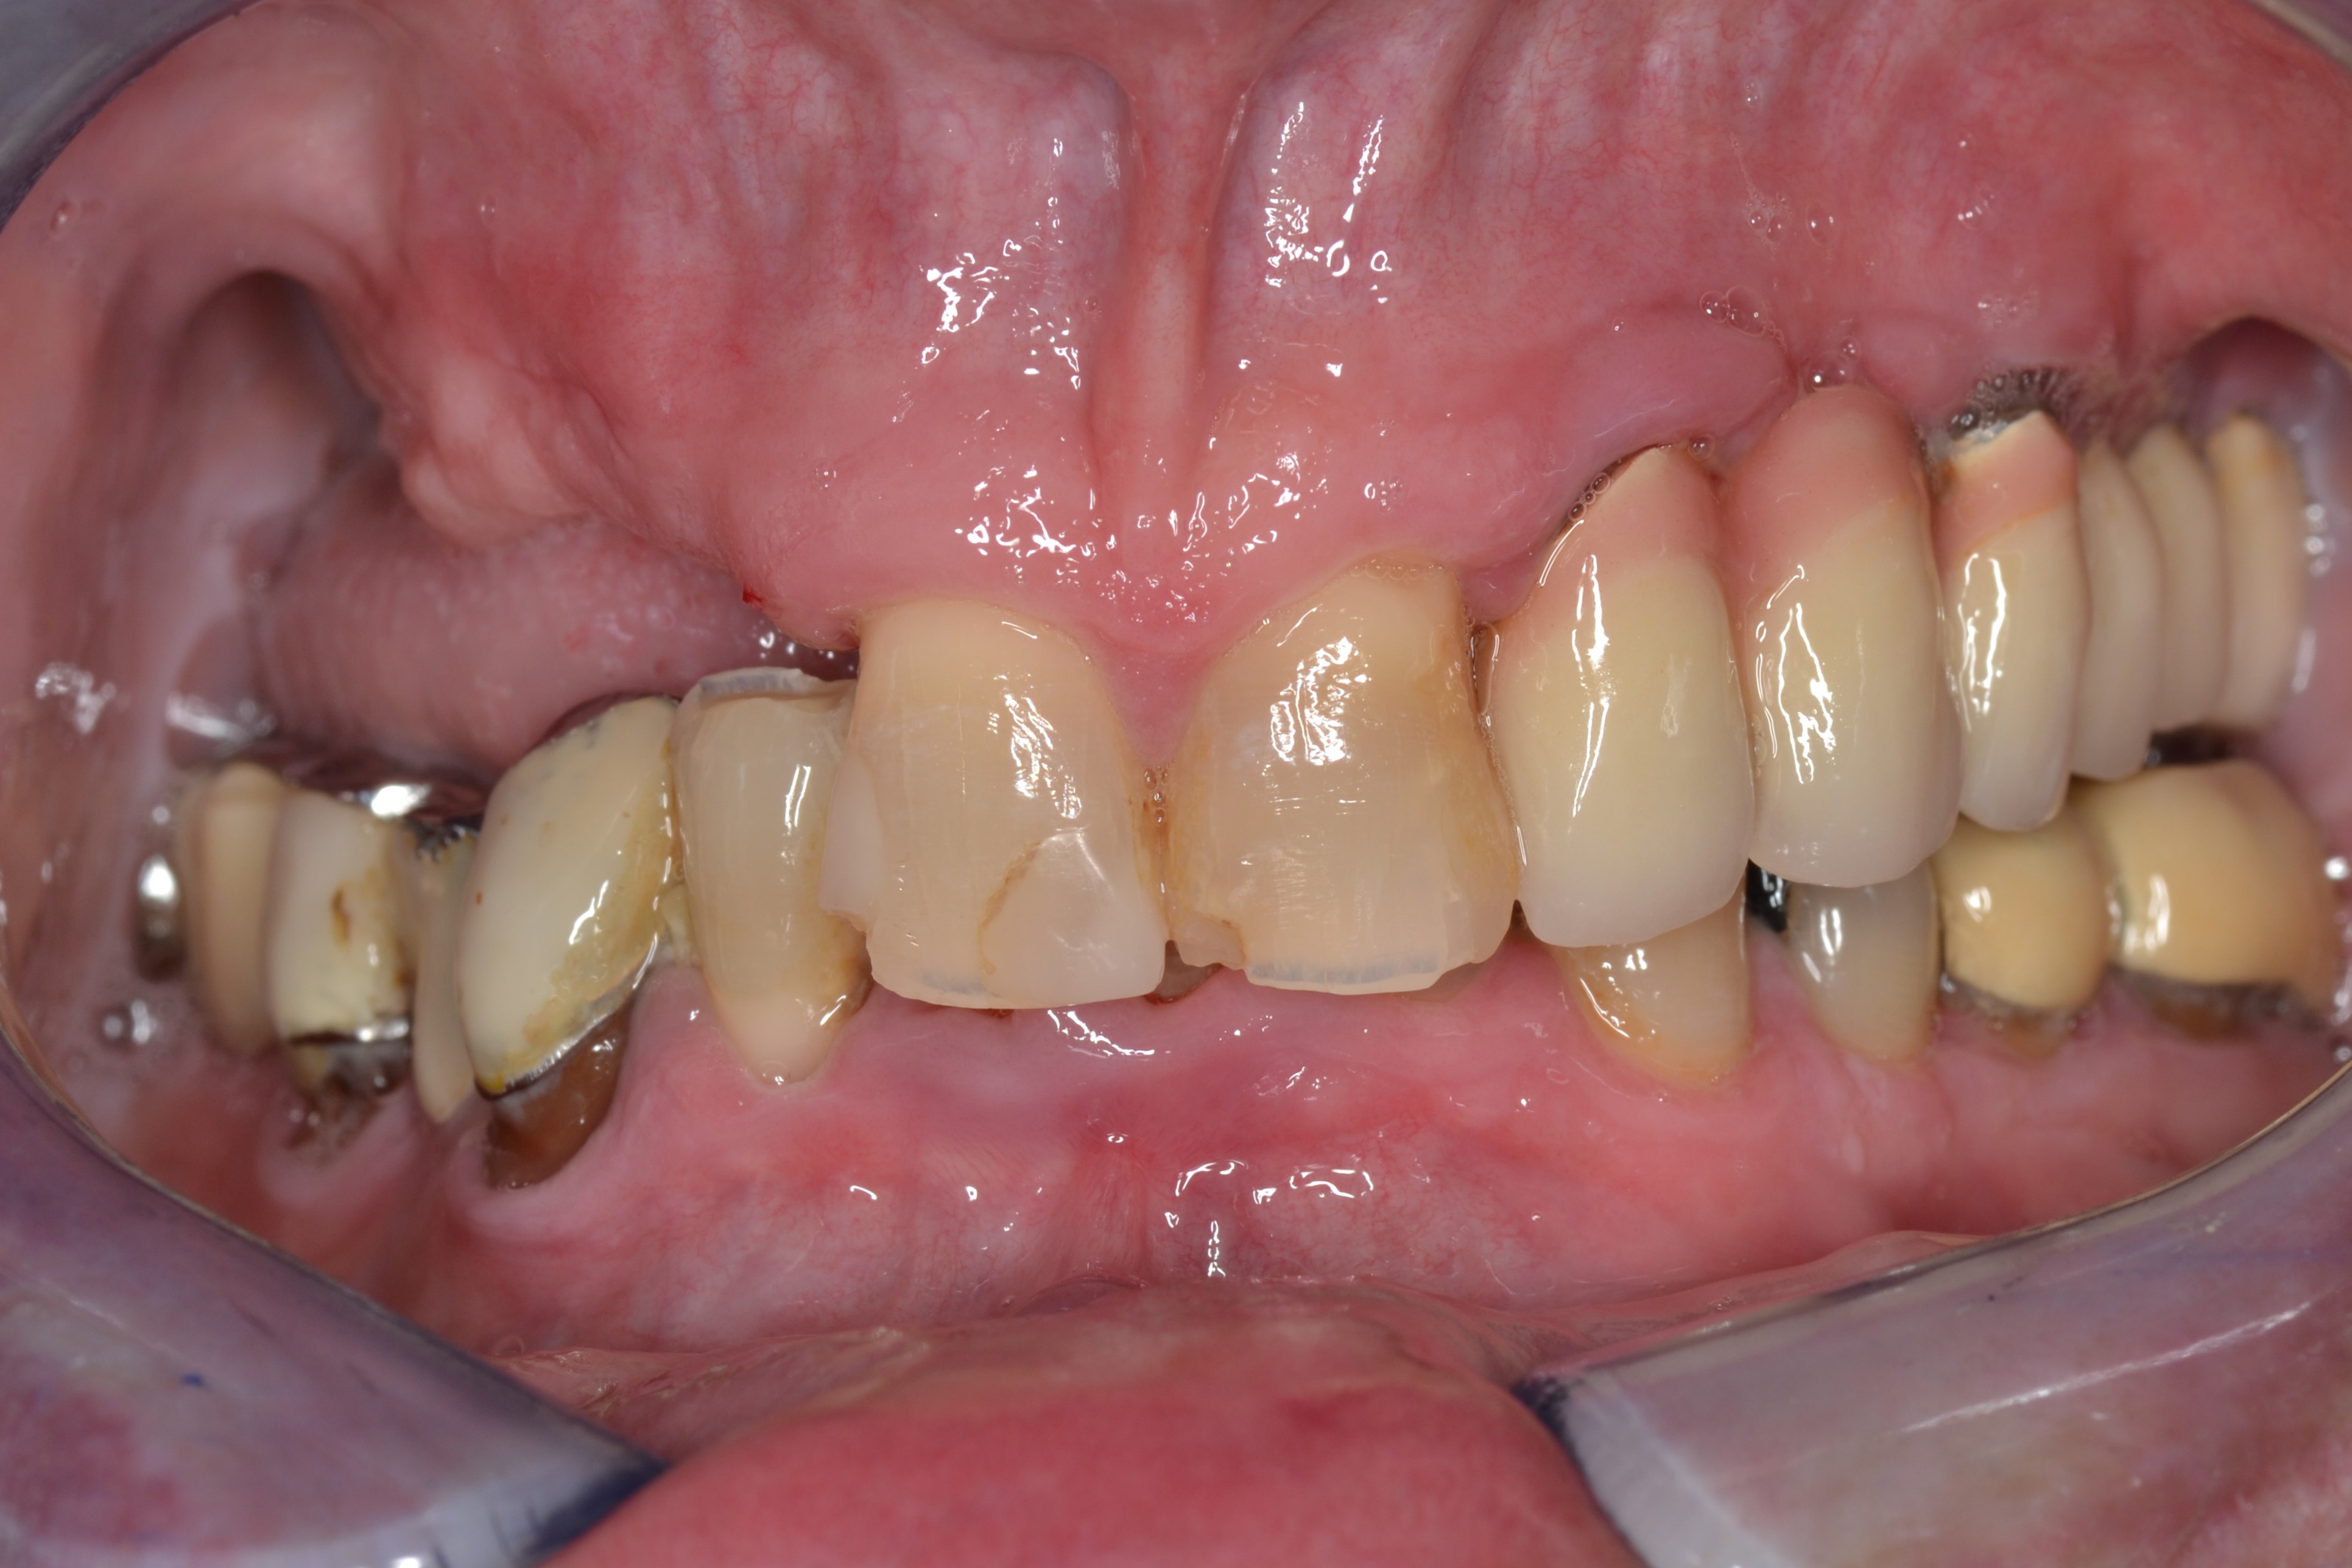

This 60-years old patient was missing a few teeth in his upper right jaw.The remaining teeth were mobile and tender when eating.

We extracted the remaining upper teeth and made him a full acrylic denture.